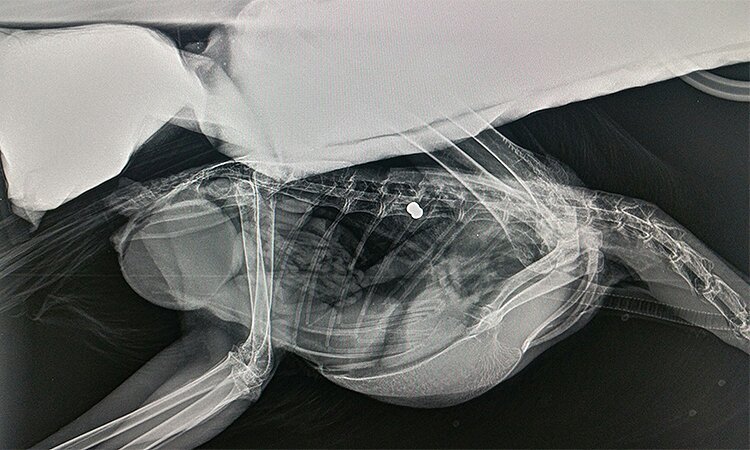

X-rays showed a pellet lodged in its spine and since this rendered the bird unable to stand or fly, sadly it had to be humanely destroyed.